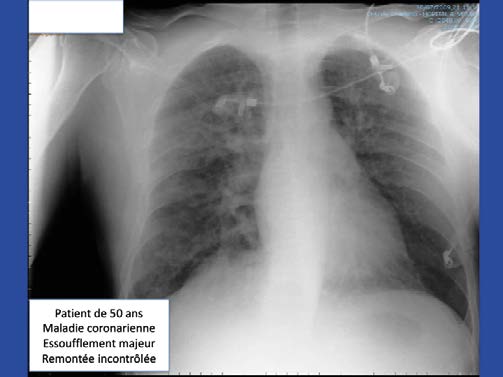

La prévalence de cet accident n’est pas négligeable : 3 déclarations d’oedème pulmonaire d’immersion (OPI) en 2023 à la Lifras ! 2 déclara-tions après une plongée bouteille et 1 déclaration au cours d’une plongée en apnée.

L’OPI se définit par la présence de liquide dans l’alvéole suite à la rupture de la barrière alvéolo-capillaire, ce qui empêche l’oxygénation normale de l’organisme. L’OPI touche principalement les sujets âgés de plus de 45 ans et hypertendus, mais survient aussi chez des sujets jeunes avec un coeur sain.

- Difficultés respiratoires (dyspnée), râles bronchiques facilement audibles ;

- Toux ;

- Expectorations de sang ou de mousse rosée, suivies éventuellement d’une syncope hypoxémique ;

- Surpression pulmonaire par remontée rapide et difficultés respiratoires ;

- Décès en immersion ou en surface.